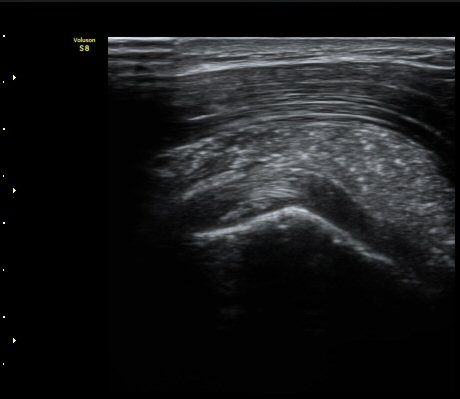

ÁÖ»ç ÈíÀΰú Á¡¾×³¶³» ÁÖ»çÄ¡·á(÷ºÎ ÆÄÀÏ) 1ÀÏ ÈÄ ½ÃÇàÇÑ °Ë»ç¿¡¼­ Á¡¾×³¶ÀÇ ºÎÁ¾ ¹× ¼®È¸ÀÇ

Á¦°Å°¡ °üÂû µÊ(±×¸² 6, 7).